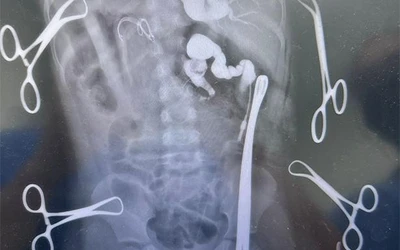

Reconstruyen vía biliar de una menor en HGZ 71 del IMSS Veracruz

Para tal efecto, se utilizó un segmento del intestino.